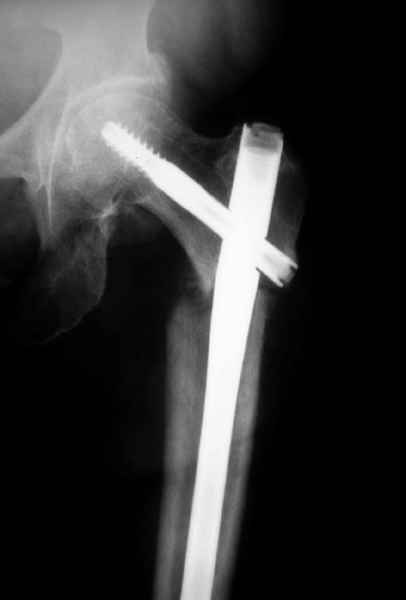

Михаил, здравствуйте. Если присмотреться - на четвертом снимке есть перелом гвоздя по отверстию.

Видимо, проблем тут две: во-1-х, центральный отломок был оставлен в варусно-сгибательной установке, во-2-х, не динамизировали вовремя.

Нижние винты хотели сломаться, но, увы, один не сломался, и тогда сломался гвоздь. Хотя и при динамизации в таком положении отломков

могло не срастись.